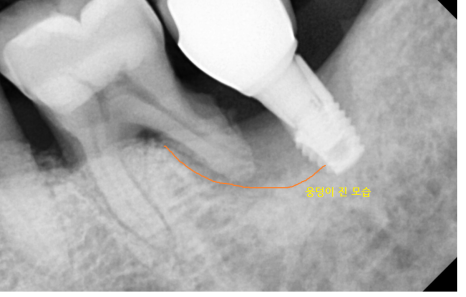

임플란트를 심고나서의 예후도

진단을 할 때 중요한 부분입니다.

웅덩이 진 부분에

뼈 가루를 넣어서 보강해주는거죠~!